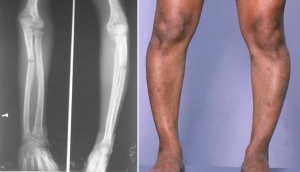

Raşitizm, çoğunlukla D vitamini eksikliğine bağlı olan, genellikle 6-18 aylık çocuklarda görülen kemik hastalığıdır. Kemik oluşumunun tam olmaması nedeniyle tedavisi geciktirilmiş, ihmal edilmiş hastalarda uzun kemiklerde şekil bozukluğu olur.

Günümüzde ender rastlanan bir hastalık olan, oysa 19. yüzyıl başlarında Kuzey Avrupa ülkelerinde doğan çocukların yaklaşık %90’ının 4 yaşına gelmeden ölmelerine yol açan raşitizm, omurga, kol ve bacak kemiklerinde biçim bozukluklarına yol açar. Başlıca nedeni güneş yetersizliğine bağlı D vitamini eksikliğidir. Çok ender rastlanan bir nedeni de, bazı böbrek borucukları hastalıklarıdır. D vitamini eksikliğinden kaynaklanan raşitizm, biçim bozuklukları bırakarak kendiliğinden iyileşme gösterir. D vitamini iyileşmeyi sağlasa da, doğuştan başlanarak 18. aya ya da 2 yaşına kadar D vitamini vermek yoluyla ortaya çıkmasını önlemek daha doğru bir yöntem olur.

Raşitizmin diğer belirtileri, kemiklerde kalsiyum birikiminin yetersizliğine bağlıdır. Raşitizmde kemik belirtileri önce kafa kemiklerinde, 4- 10 aylıkken göğüs kafesinde, altı aydan sonra kol ve bacaklarda görülür. Bunun nedeni, D vitamini eksikliğinin etkisinin hızlı büyüyen kemiklerde daha belirgin olmasıdır.